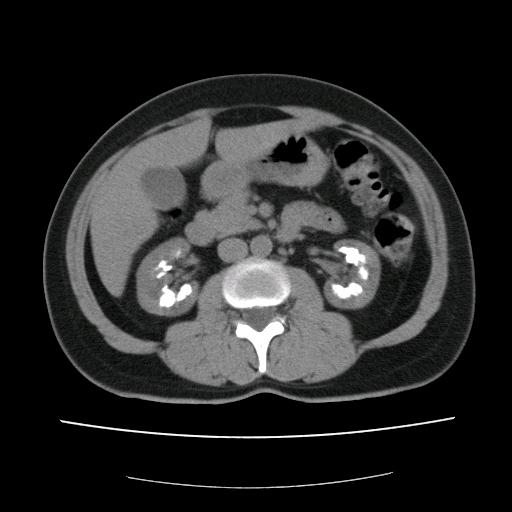

Een 52-jarige vrouw presenteerde zich op de polikliniek Urologie vanwege recidiverende urineweginfecties en pijn in de linker flank. Anamnestisch had patiënte sinds 20 jaar last van urolithiasis en daarbij had zij meerdere malen nierstenen uitgeplast. Een abdominale CT-scan toonde beiderzijds uitgebreide calcificaties van de nier. Een buikoverzichtsfoto liet tevens een niersteen in de linker ureter zien.